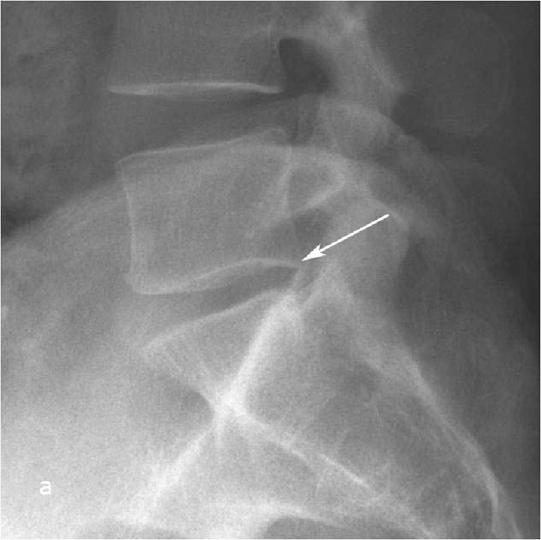

При рентгенографии (Рис.7) и МРТ (Рис.8) поясничного отдела позвоночника выявляется дегенеративный ретролистез L5 позвонка, секвестрированная  парамедианная грыжа мп диска L5-S1  слева.

Рис. 8а. Рентгенограмма поясничного отдела позвоночника в боковой (а) и прямой (b) проекциях до операции. Стрелкой показано смещение тела L5 позвонка кзади. Рис. 8b. Рентгенограмма поясничного отдела позвоночника в боковой (а) и прямой (b) проекциях до операции. Стрелкой показано смещение тела L5 позвонка кзади.

Рис. 7а,b. Рентгенограмма поясничного отдела позвоночника в боковой (а) и прямой (b) проекциях до операции. Стрелкой показано смещение тела L5 позвонка кзади.